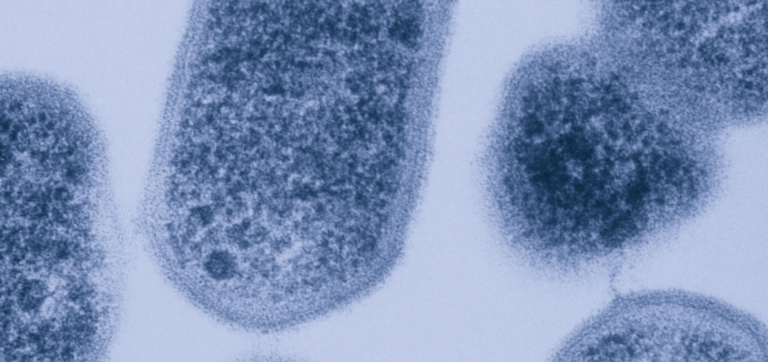

The second category of vaginal infection occurs when microbial pathogens are introduced into the vagina from a sexual partner. Chlamydia, caused by the bacteria Chlamydia trachomatis, is the most frequently reported bacterial sexually transmitted infection (STI) in the U.S.8

Once Chlamydia trachomatis enters the body, it adheres to and penetrates cells lining the vagina, where it can evade immune attack and replicate. Vaginal microbiomes that contain species of bacteria such as Lactobacillus crispatus and Lactobacillus jensenii have been shown to actively protect against chlamydia infection, likely due to the forms of lactic acid they produce.9

Chlamydia return rates tell a similar story. The infection is often treated with antibiotics including azithromycin or doxycycline and around 25% of women treated will have a repeat infection. These could be caused by remaining remnants of the initial infection, resistance to the original antibiotic used, or a reinfection by a new strain of Chlamydia trachomatis.11